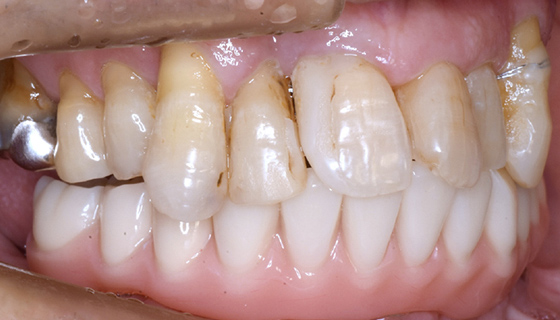

治療前

この症例では下顎の歯周病が特に進行していて、歯がクラグラで噛みにくい為、下の歯を抜歯してオールオン4で治療、上は特に歯周病が進行している左側の大臼歯を抜歯して経過観察することにしました。